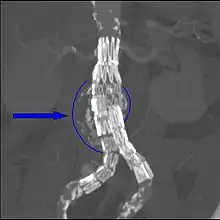

Durability and problems such as 'endoleaks' may require careful surveillance and adjuvant procedures to ensure the success of the EVAR or EVAR/hybrid procedure. CT angiography (CTA) imaging has, in particular, made a key contribution to planning, success, durability in this complex area of vascular surgery.